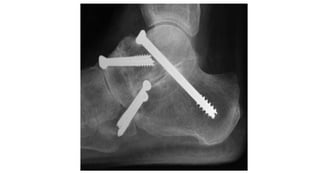

• Percutaneous 6.5-mm or 7.0-mm screws can be placed across the joint with the

help of fluoroscopy.

• The ankle is appropriately positioned (5° of valgus, 0° of dorsiflexion, and neutral

rotation)

• Cannulated screws are inserted, the position is checked fluoroscopically, and the

wound is closed